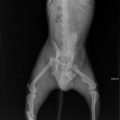

Tagumise käpa luumurd.

Koerake sattus varjupaika vigastatud käpaga. Ülevaatusel selgus, et koera käpal on mitmekordne luumurd. Pidime paigaldama ka kateetri, kuna ta ei saanud pissida (ilmselt autolöögist põhjustatud kusepõie atoonia).

Собака поступила в приют с множественным переломом ноги. Не могла пописать (видимо был удар машины и, как результат, атония мочевого пузыря). Нога в очень тяжёлом состоянии, и завтра мы кладём собаку на операционный стол.